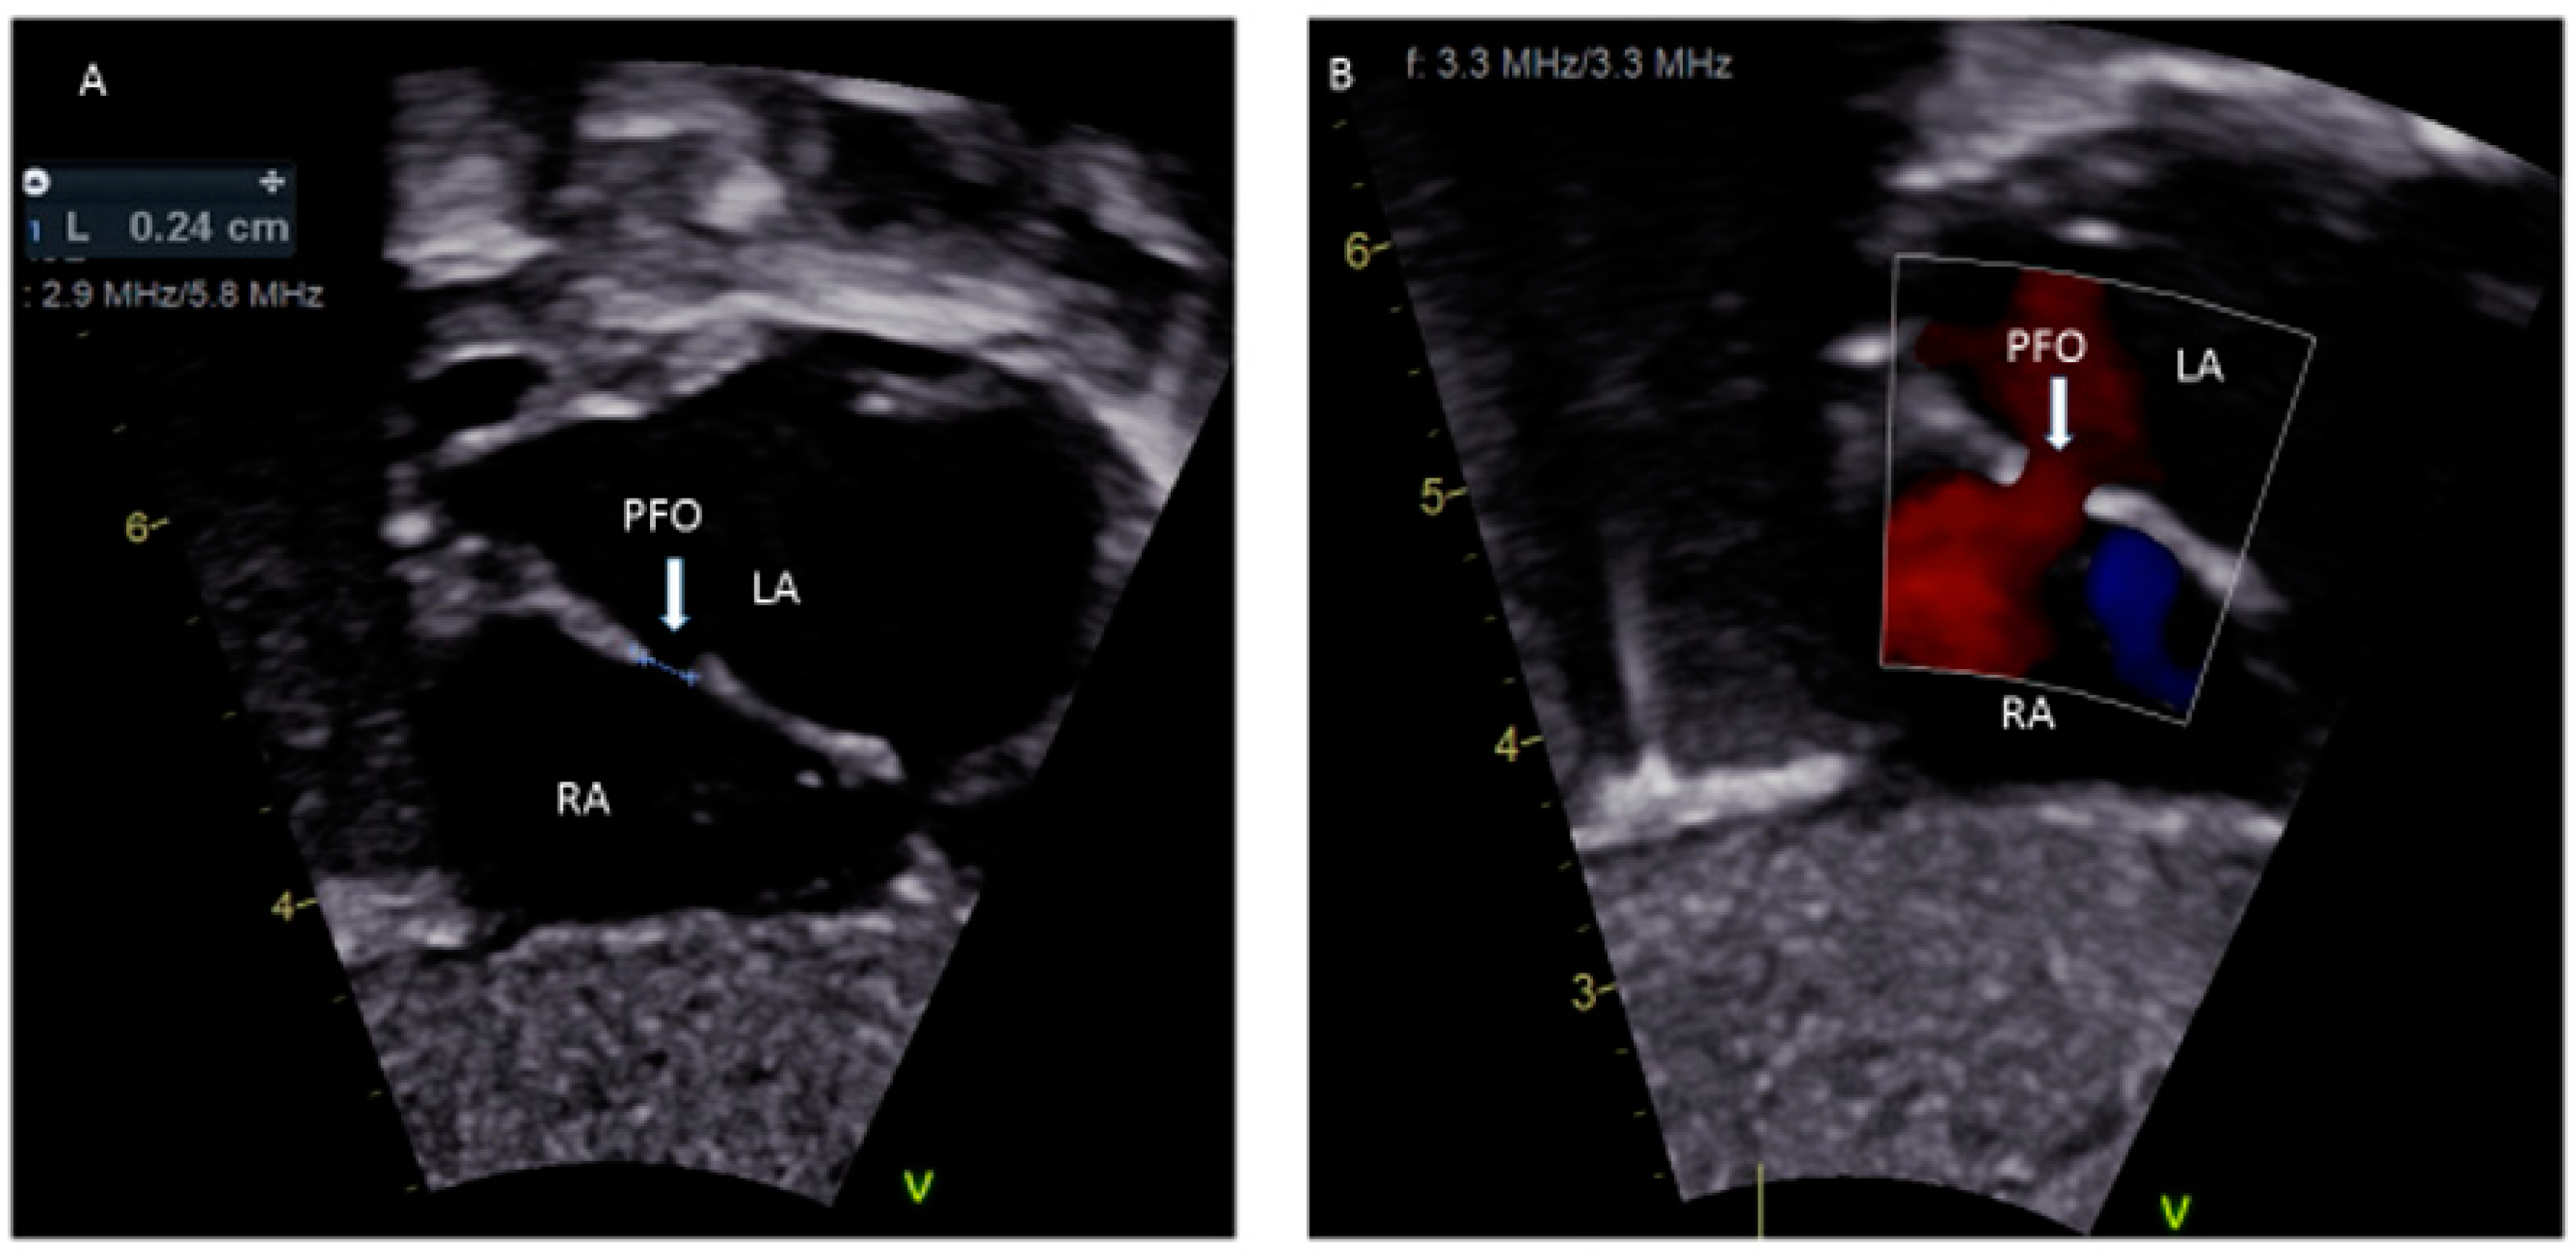

- Silvestry, F.E. Guidelines for the echocardiographic assessment of atrial septal defect and patent foramen ovale from the American Society of Echocardiography for cardiac angiography and interventions. J. Am. Soc. Echocardiogr. 2015, 28, 910–985. [Google Scholar] [CrossRef]

- Rana, B.S.; Shapiro, L.M.; McCarthy, K.P.; Ho, S.Y. Three-dimensional imaging of the atrial septum and patent foramen ovale anatomy: Defining the morphological phenotypes of patent foramen ovale. Eur. J. Echocardiogr. 2010, 11, 119–125. [Google Scholar] [CrossRef]